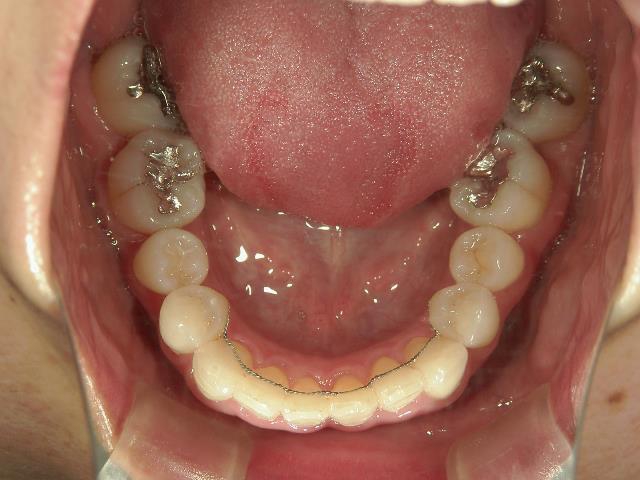

矯正歯科 治療前矯正歯科 治療前

プチワイヤー矯正 症例(23

41歳女性 浜松市浜北区在住

治療期間 1年3カ月

主訴:下の前歯の歯並びが乱れていて、舌に当たって痛い。

矯正_灰色.pngno.41_8994_治療前_下.JPG矯正_灰色.png